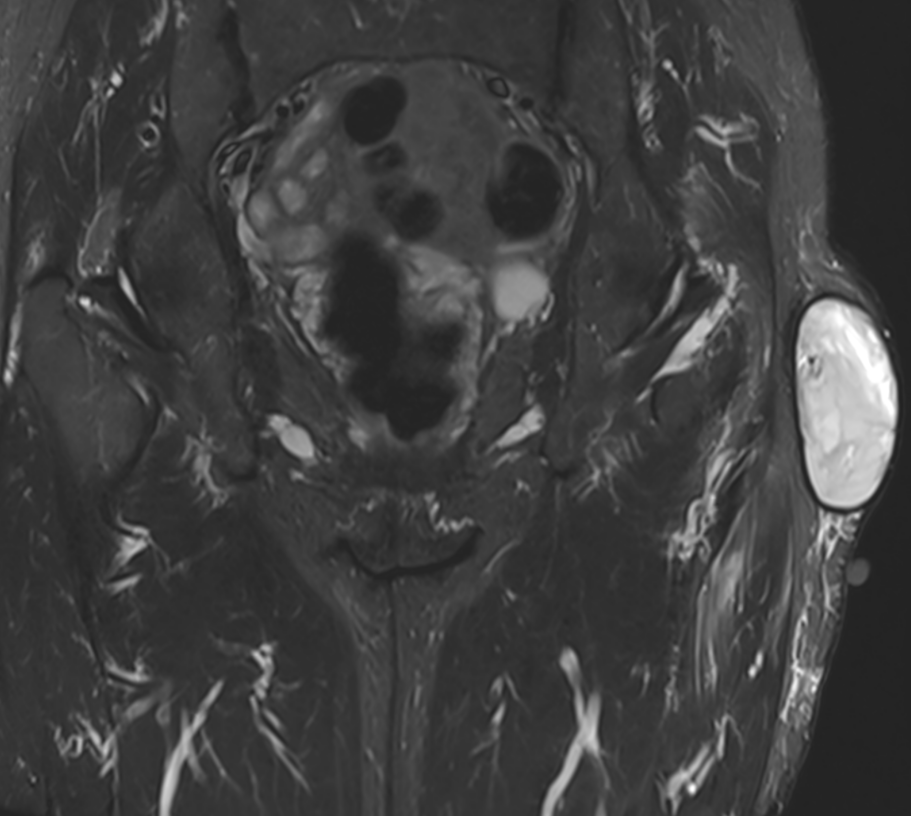

3. Morel Lavallée lesion over greater trochanter